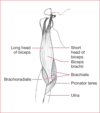

Elbow Flexion

Biceps Brachii, Brachialis, Brachioradialis, Pronator teres